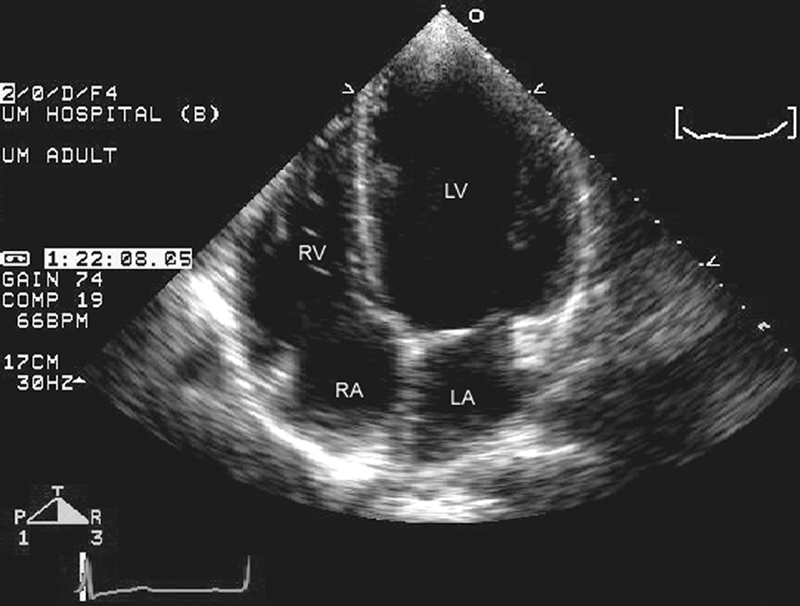

فحوصات تشخيصية لبعض امراض القلب والشرايين التاجية